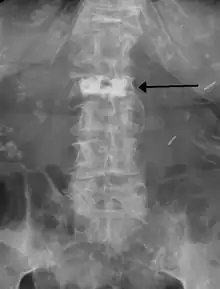

During the procedure, bone cement is injected with a biopsy needle into the collapsed or fractured vertebra. The needle is placed with fluoroscopic x-ray guidance. The cement (most commonly poly methyl methacrylate (PMMA), although more modern cements are used as well) quickly hardens and forms a support structure within the vertebra that provide stabilization and strength. The needle makes a small puncture in the patient's skin that is easily covered with a small bandage after the procedure.[2]

Some of the associated risks are from the leak of acrylic cement to outside of the vertebral body. Although severe complications are extremely rare, infection, bleeding, numbness, tingling, headache, and paralysis may ensue because of misplacement of the needle or cement. This particular risk is decreased by the use of X-ray or other radiological imaging to ensure proper placement of the cement.[2] In those who have fractures due to cancer, the risk of serious adverse events appears to be greater at 2%.[23]